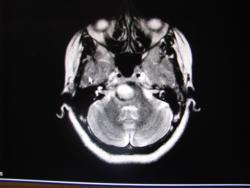

Округлое объёмное образование ствола мозга (моста) с чёткими контурами, высоким ярким сигналом на Т1, Т2 и FLAIR; на Т2 виден уровень жидкость-жидкость. По периферии, заднему и передне-медиальному краю участки полуциркулярной гипоинтенсивности. Думаю о тератодермоиде (эпидермоидная киста).

поверьте на слово, при использовани программы с жироподавлением интенсивность сигнала не изменилась.По нижнему контуру образования пролеживается зона гетерогенного сигнала с гипоинтенсивным ободком.здесь картинки статичны, а на полном исследовании эта зона очень хорошо видна - кавернома. Поэтому я решила что это подострая стволовая гематома как следствие кровоизлияния из каверномы.

Тёмная полоска это за счёт продуктов распада гемоглобина, указывает на кровоизлияние... Чисто по картинке-это может быть каверномой, жаль что не опубликованы были срезы с подавлением сигнала от жира, я поэтому и высказался по началу в пользу тератодермоида.

кавернома имеет очань характерный вид - гетерогенный "сетчатый" характер с гипоинтенсивным кольцом гемосидерина , в них нет участков "быстого" кровтотока , крупных питающих сосудов и дренирующих вен.В даннм случае она очень небольшого размера .кстати очань часто причиной гематом ствола мозга являются срытые ( оккультные)т сосудистые мальформации.